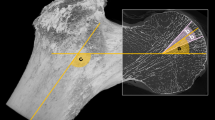

Trabecular bone explants from the femoral head of patients with ONFH were obtained intraoperatively with a curette during THA (Fig. 1). Cylindrical specimens of trabecular bone from the intertrochanteric region, located distant from the necrotic lesion, were obtained during femoral preparation using a box osteotome. Bone samples from the same anatomical sites in patients with OA were collected as controls for comparison with the ONFH samples. Due to the small size of the explants, samples from eight patients in each group were used for imaging techniques, while samples from the remaining patients were used for transcriptomic analyses.

Preoperative anteroposterior radiograph of a right hip in a 61-year-old man with osteoarthritis (OA) and in a 56-year-old man with osteonecrosis of the femoral head (ONFH). Trabecular bone explants were taken from the femoral head (1) and from the intertrochanteric region (2) in both patient groups.